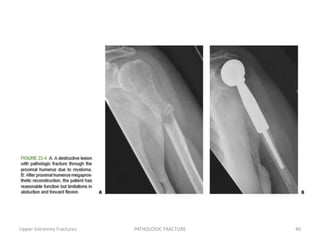

• 39.

Proximal Humerus Humeral heador neck: proximal humeral replacement or intramedullary fixation. When there is extensive destruction of the proximal humerus or a fracture leaving minimal bone for adequate fixation, resection of the lesion and reconstruction with a cemented proximal humeral endoprosthesis are indicated. In the face of distal disease progression, it can be modified to a total humeral prosthesis. Upper-Extremity Fractures PATHOLOGIC FRACTURE 39

• 40.

• 41.